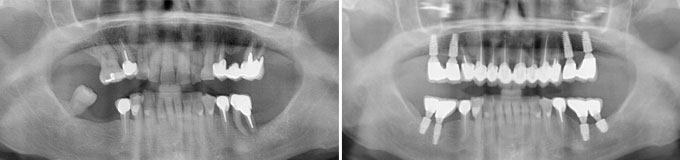

Il me manque de nombreuses dents, les autres sont perdues, je veux l’idéal.

Solution : on peut remplacer toutes vos racines manquantes ou perdues par autant de racines artificielles et vous redonner des dents fixes partout.

Toutes dents sont hélas perdues. Toutes les dents absentes sont remplacées par des couronnes sur implants.